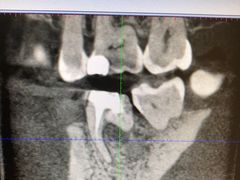

• -上海陈守平口腔诊所

blueflywang | 19-08-12

报错